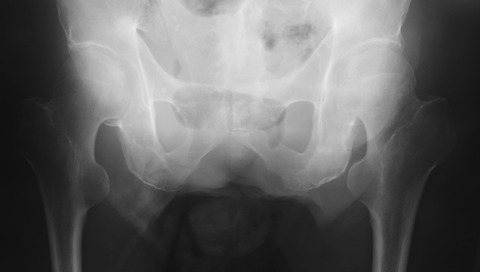

先日、アルバイト先で外来をしていた際、70歳台女性が腰背部の腫瘤を主訴に初診されました。腫瘤は以前からあって特に痛みも無いのですが、家人から指摘されて受診したそうです。

診察すると左腰背部に径10cm程度の可動性はそれなりにある弾性軟の腫瘤を触知しました。外観上は脂肪腫っぽかったのですがサイズが大きいためCTを施行しました。

CTでは左腎背側に筋欠損部が存在し、そこから筋層外に腎周囲の脂肪織と思われるlow density massの脱出を認めではないですか!

てっきり脂肪腫だと思っていたので、その日は患者さんに帰ってもらい放射線科医師の読影を待ちました。しかし、放射線科医師の読影結果は、なんと「脂肪腫」でした・・・。

おかしいなぁ と思いながらも脂肪腫ならば、とMRIを依頼しました。しかし、MRIの画像を確認すると明らかに背筋が欠損しており、腫瘤は後腹膜の脂肪組織と連続していました。

外科医師に相談すると、これは特発性の「上腰ヘルニア」ではないかとのことでした。患者さんの腰背部腫瘤を触知すると、患者さんの発声が腫瘤を通じてダイレクトに私の手に伝わります。

これは明らかにヘルニアです・・・。放射線科医師の読影を鵜呑みにして”腫瘍切除術”を施行するとエライ目に会うところでした。放射線科医師の読影と言えども盲信してはいけないようです。